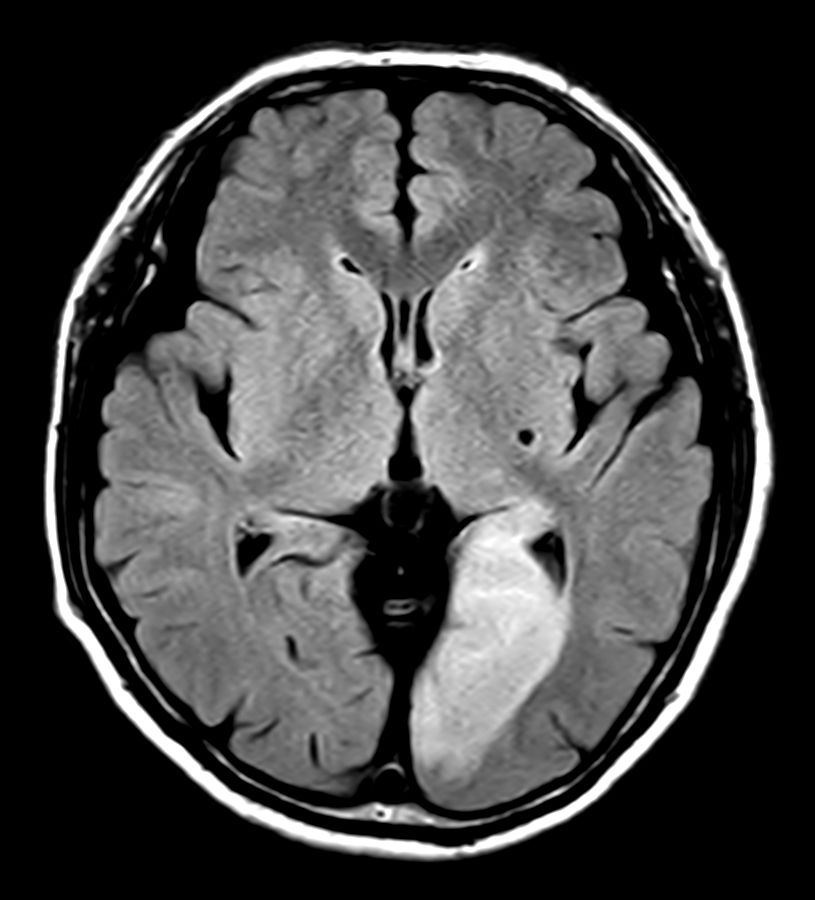

Brain infarction

Patient with a brain infarction. Compressed SENSE is used to shorten the total exam time.

T2w FLAIR - Compressed SENSE

Diffusion - b1000 (ADC)